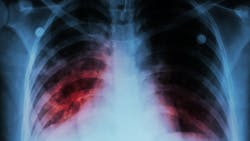

Despite countries making bold commitments to end TB by 2030, in the Sustainable Development Goals, the WHO End TB Strategy, and the 2018 political declaration on the fight against TB, the epidemic shows no sign of slowing down. In 2021, approximately 10.6 million people fell sick with TB, and 1.6 million died. Drug-resistance continues to be a major problem with close to half a million people developing drug-resistant TB every year.

BCG is currently the only licensed TB vaccine. While it provides moderate efficacy in preventing severe forms of TB in infants and young children, it does not adequately protect adolescents and adults, who account for close to 90% of TB transmissions globally.